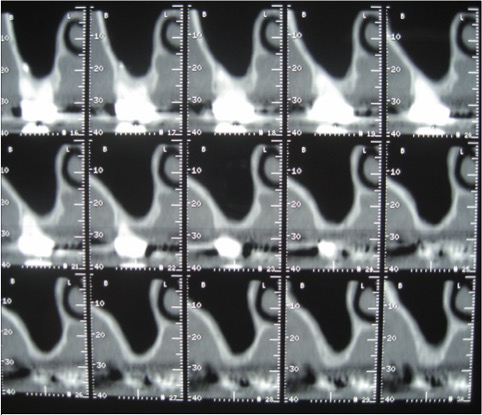

photos sinus lift avant et après la greffe osseuse

Ce comblement est réalisé en soulevant par voie latérale la muqueuse sinusienne et en interposant une greffe autogène ou d’autre nature sous celle-ci.